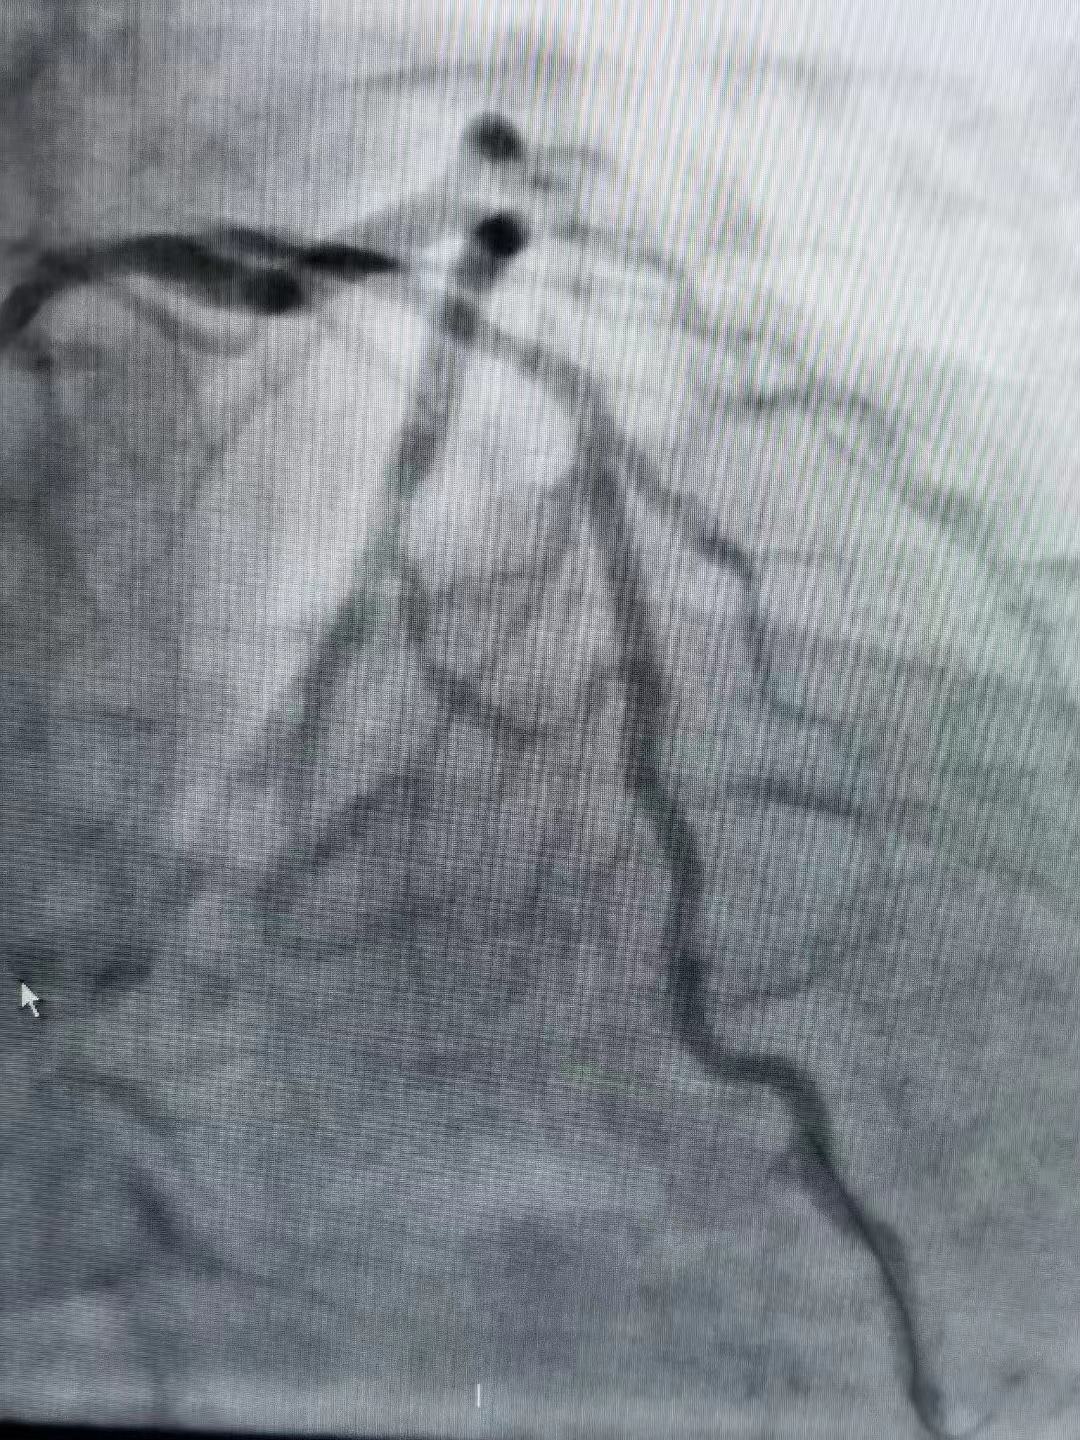

祝賀遼陽遼化醫院和海城市中心醫院相繼成功為患者植入Xinsorb生物可吸收支架

祝賀遼陽遼化醫院和海城市中心醫院相繼成功為患者植入Xinsorb生物可吸收支架!